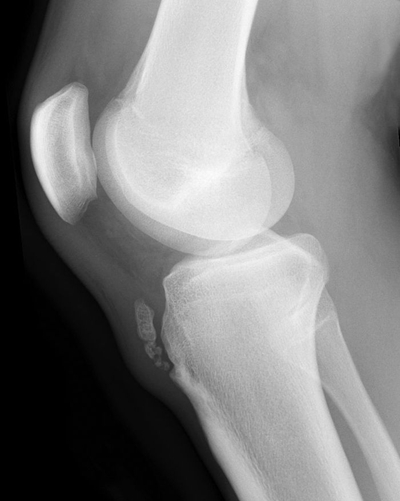

血常規、X線檢查

脛骨結節骨骺炎 (50)